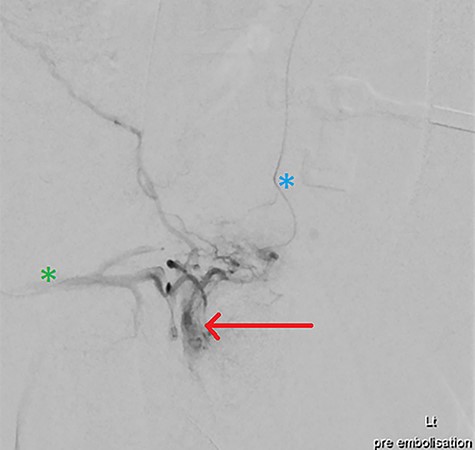

Heparin (3000 IU) was provided. Given contralateral feeding vessels, the right CFA was cannulated with the aforementioned steps mirrored, placing a microcatheter in the pseudoaneurysm via the left IPA. Two Target Neurovascular Microcoils (Stryker) were deployed at the pseudoaneurysm neck, with bilateral microcatheter angiography confirming satisfactory occlusion (Figs 4 and 5). All devices were removed, with Proglide (Abbott) arterial closure.

DSA demonstrating significantly reduced flow into the cavernosal artery pseudoaneurysm post-coil embolization (red arrow); note the left (blue asterix) and right (green asterix) distal branches of bilateral internal pudendal arteries for reference.

Final intraoperative fluoroscopic image demonstrating microcoil placement (red arrow); note the microcatheter placement within the left (blue asterix) and right (green asterix) distal branches of bilateral internal pudendal arteries for reference